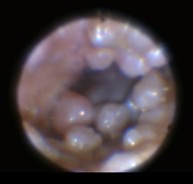

こちらはデジタルオトスコープという、カメラで耳の中を見ることが出来る機械で撮影した写真です。

↑治療開始初期は、耳垢の量が多く、耳道は腫れて狭窄していました。両側の耳道には無数の大⼩様々なできものがあり、⿎膜はできものに障害され観察することができませんでした。